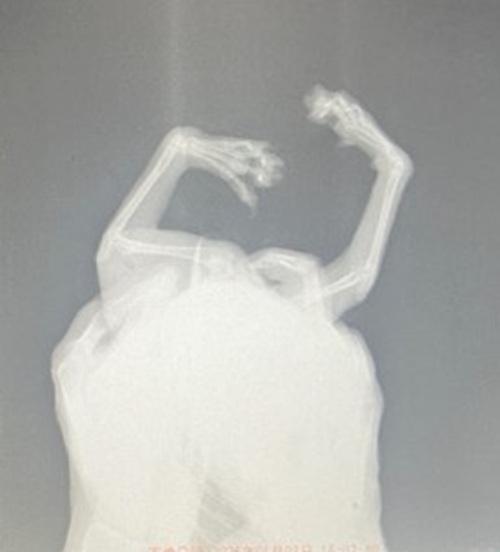

猫種はナポレオン(ミヌエット)で、長毛のとても柔らかい被毛を持っています。

この被毛は十分な手入れがなされなければ、悲惨な状態になってしまいます。

その結果、汚れ絡まった被毛が陰部全体を塞ぎ、排尿さえできなくなり、生命まで脅かすことになってしまったのがコピちゃんでした。

猫種:ナポレオン(ミヌエット)

両前肢手根関節の変形

歩行異常あり

レントゲン検査の結果、両前肢の変形は先天性のものと診断されました。